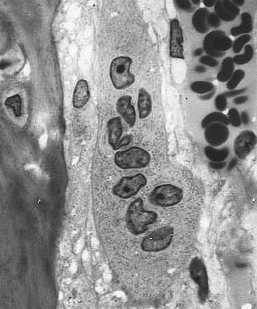

“One of the main unanswered questions in relation to initiation of bone metastasis is how changes to the bone microenvironment, including accelerated bone turnover, affects disseminated tumor cells in bone,” wrote researchers led by Penelope D. Ottewell, PhD, of the University of Sheffield in the United Kingdom. Her group tested whether interruption of the interaction between a protein called RANK and its ligand (RANKL), which is essential for osteoclastogenesis, could stop the proliferation of the dormant tumor cells. Results were published online ahead of print on February 2 in the International Journal of Cancer.

In an in vivo study involving mice, researchers administered OPG-Fc, which blocks the RANK-RANKL interactions. They tested this in some mice that had undergone ovariectomy, which is known to increase bone turnover and thus possibly initiate tumor cell proliferation. Fourteen mice in each of two groups were injected with either saline or with OPG-Fc, and half of each of those groups also had undergone ovariectomy. In the saline group, 78.5% of the ovariectomy mice developed long bone tumors by day 35; only 14.5% of those who underwent a sham ovariectomy procedure developed tumors.